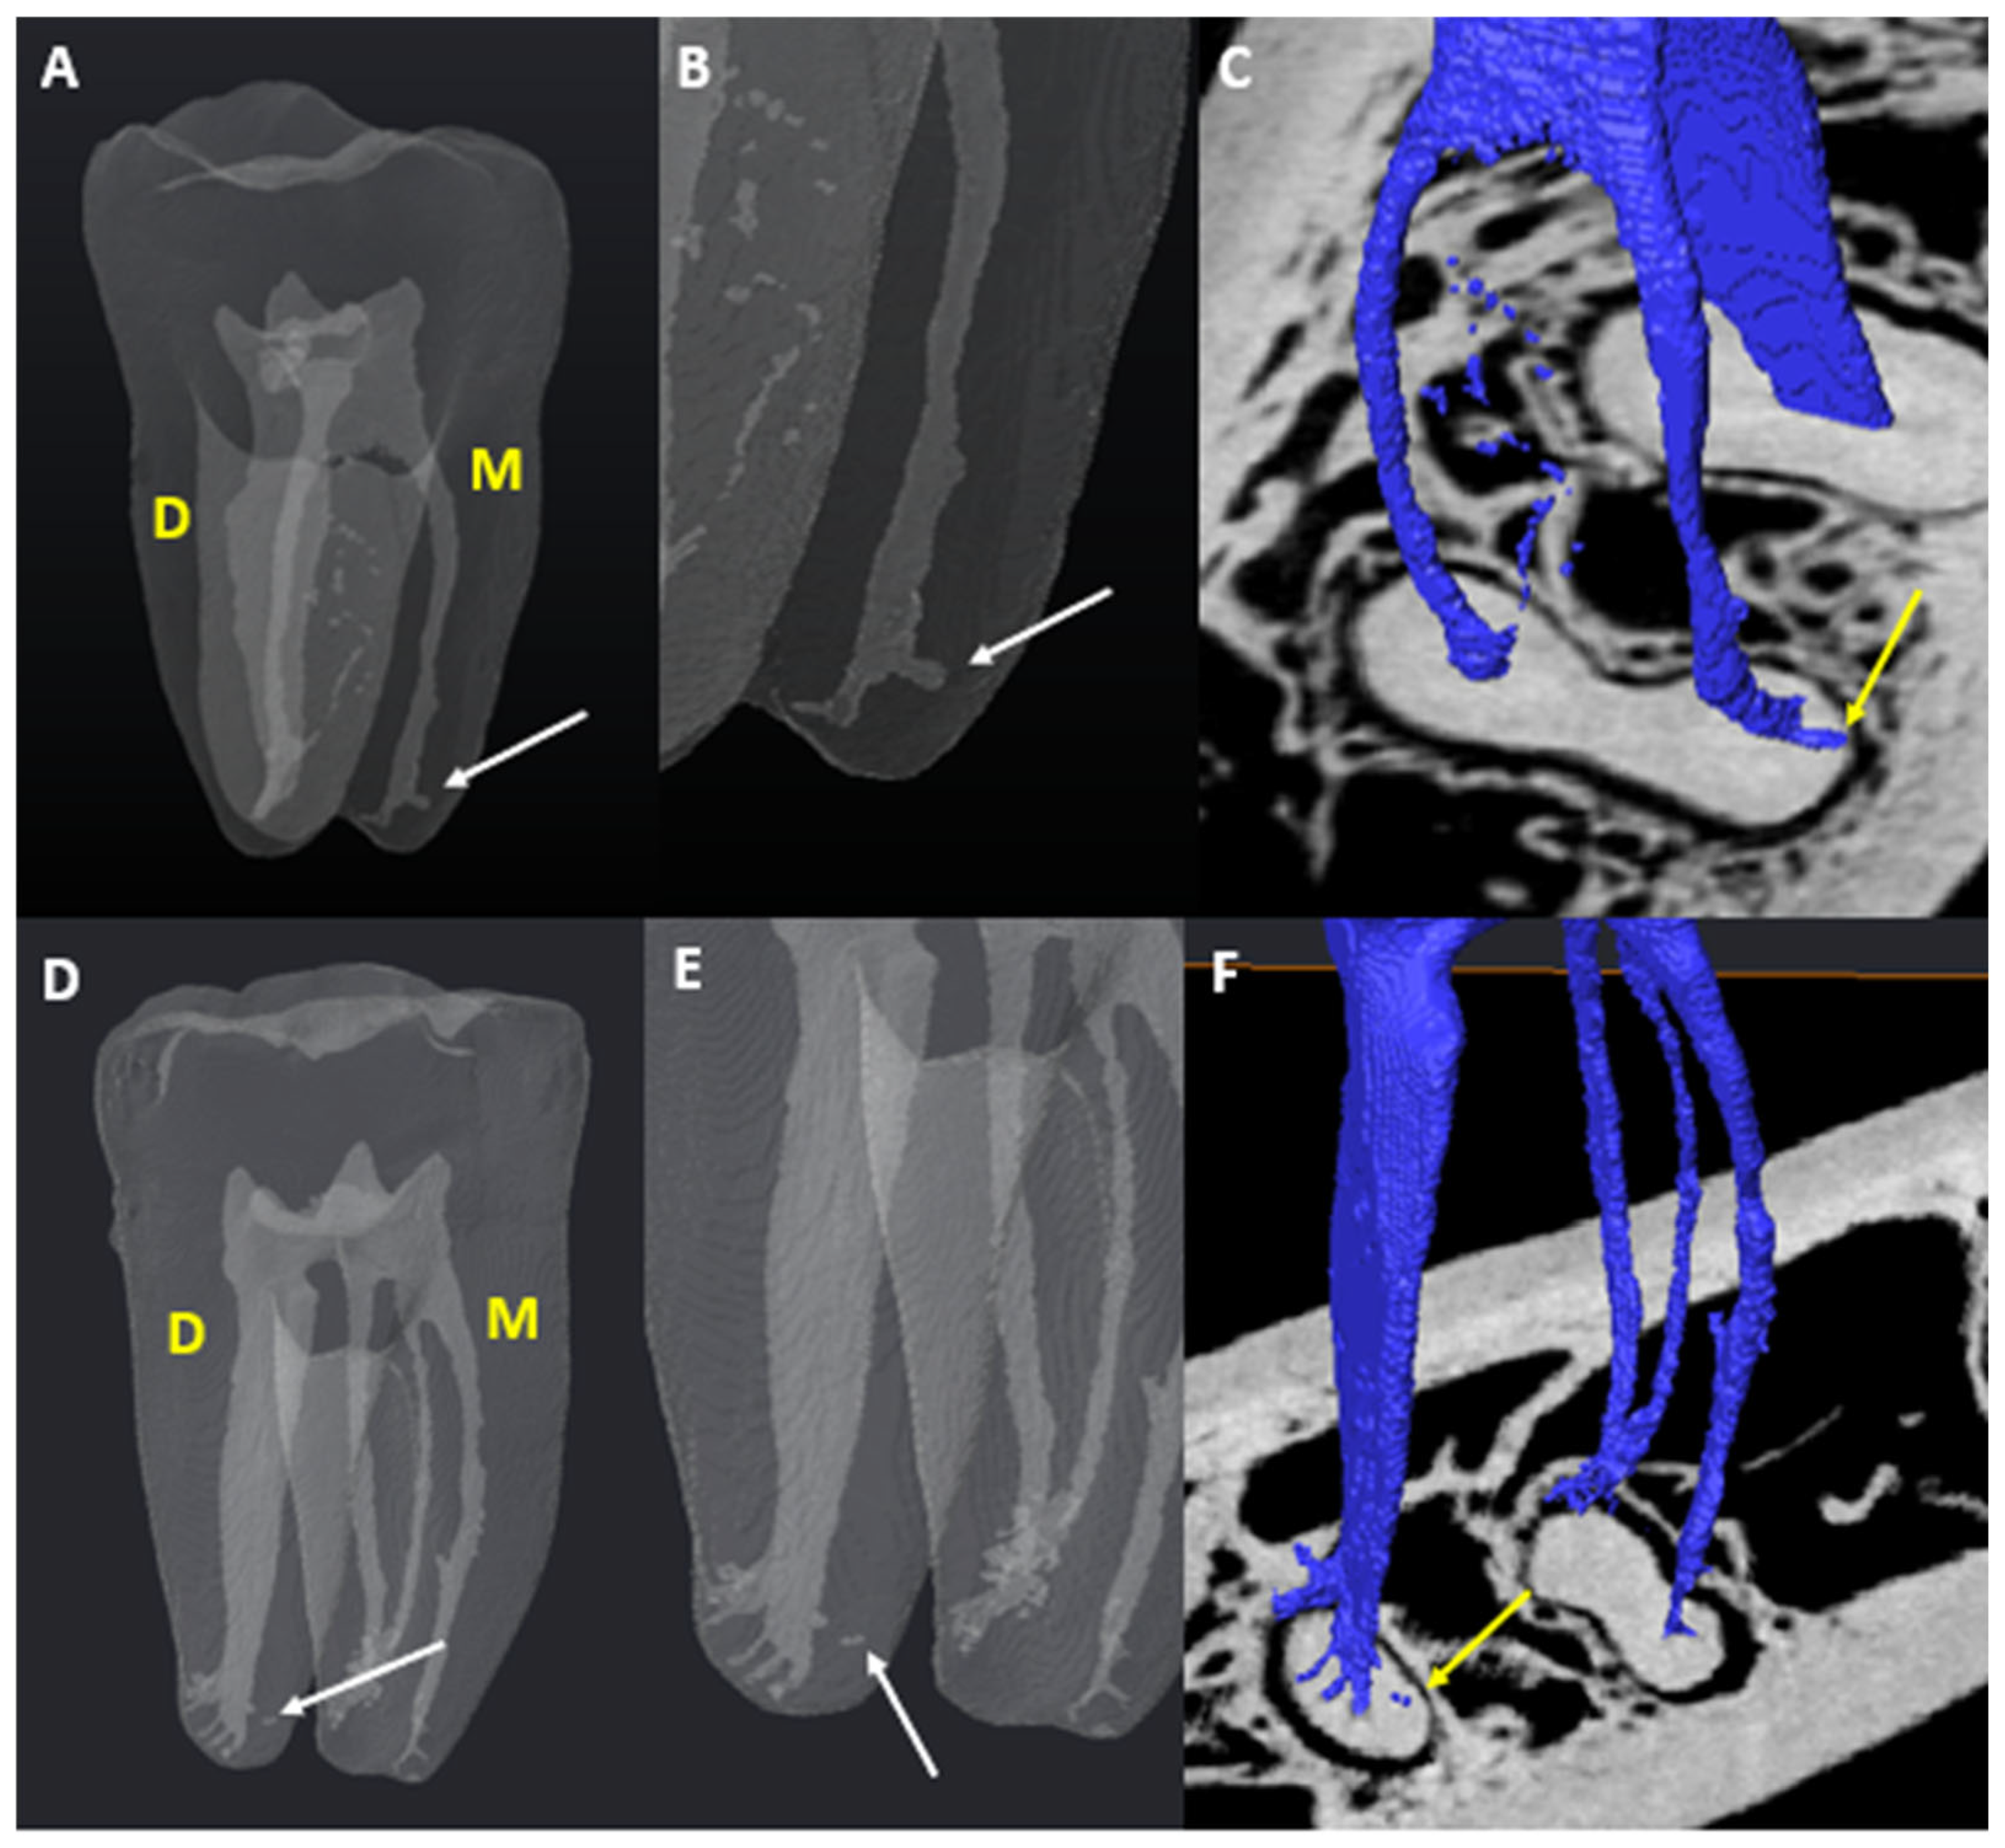

3.3. Number of Canals per Root

3.4. Chamber Canals

3.5. Accessory Canals (ACs)

3.5.1. M Root

3.5.2. D Root